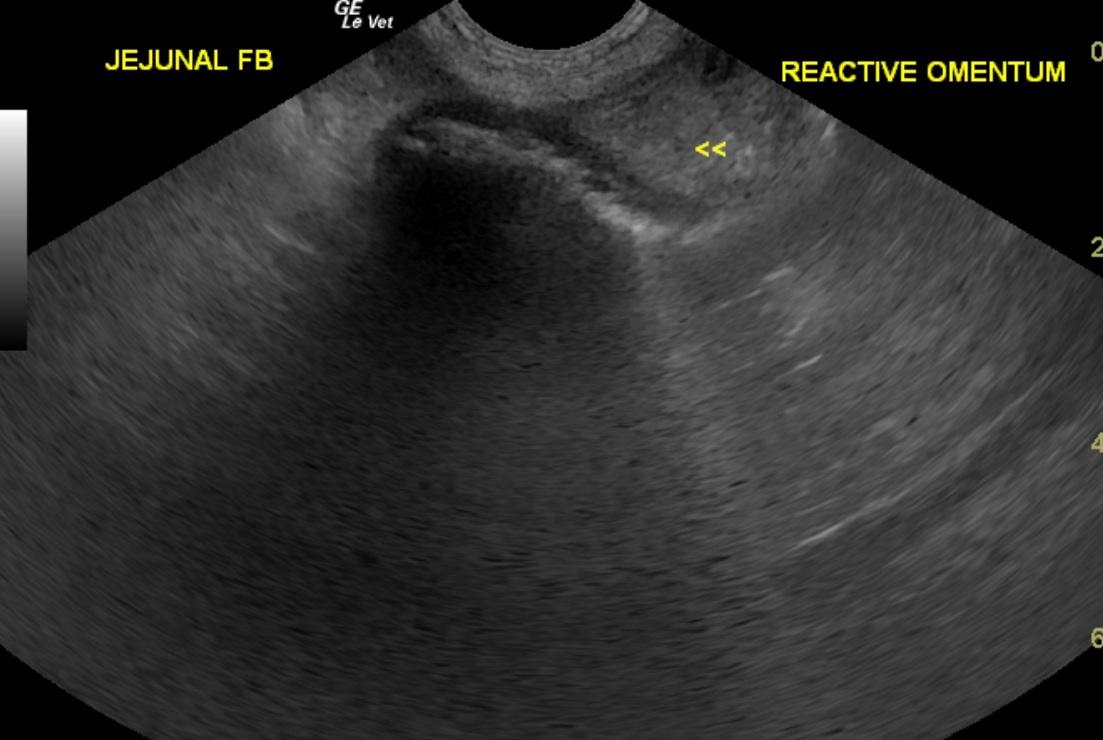

A 7-year-old MN Dachshund was presented for anorexia, dehydration, and vomiting for two days. Recent CBC and chemistry panel had shown elevated HCT, neutrophilia, monocytosis, low sodium, low potassium and low chloride, and elevated ALP; elevated AST activity, elevated amylase, increased anion gap, increased bicarbonate, elevated urea, elevated cholesterol, elevated creatinine, elevated phosphate and elevated CK. 4DX snap ELISA was negative and urinalysis and fecal examination within normal limits.